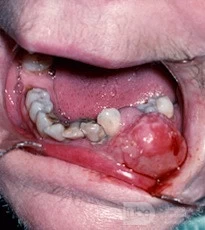

Bướu sợi

Sự khác biệt về tên của tổn thương sưng tím này phát sinh từ nướu dựa trên mô học của nó. Mô hạt trong trường hợp này ít mạch máu hơn và tổn thương chứa nhiều mô xơ hơn so với u hạt mủ.